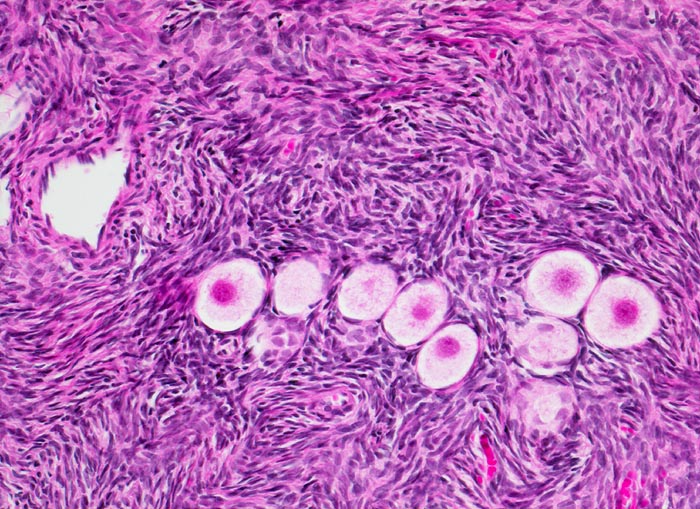

Morphologische Merkmale (1. Präparatlink):

• Tumor bestehend aus einer Mischung reifer epithelialer und mesenchymaler Gewebskomponenten:

• Das Gewebsfragment wird links oben von Magenschleimhaut vom Corpustyp bedeckt. Unmittelbar darunter finden sich hyaliner Knorpel und Kolonschleimhaut.

• Im mittleren Abschnitt des Präparates finden sich zystische Hohlräume, ausgekleidet von teils verhornendem Plattenepithel. Dieses ist assoziiert mit reichlich Talgdrüsen.

•  Unten im Bild sieht man zwei Zahnanlagen und Knochengewebe.

• Residuelles Ovarialgewebe ist nicht erkennbar.